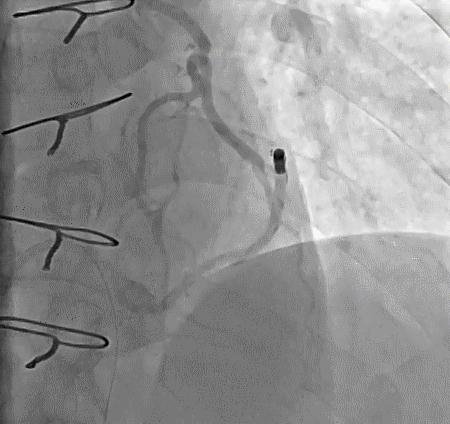

➢ CASE 1

➢ CASE 2

右冠起源异常,开口于左冠窦

➢ CASE 3

AL1.0

➢ CASE 4

➢ CASE 5

升主动脉造影未见桥血管显影,原位血管造影也没发现竞争血流迹象,可以确定桥血管已闭塞,必要时可以借助冠脉CTA辅助诊断